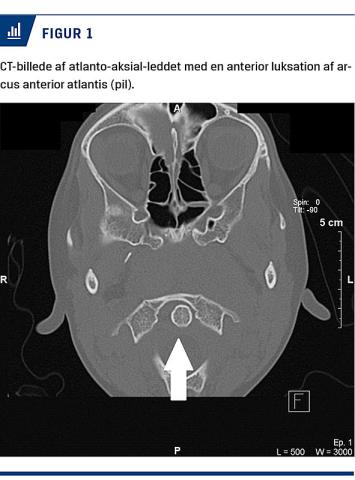

CT af cerebrum viser normale intrakranielle forhold, men bløddelshævelse i nasopharynx og anterior subluksering af arcus anterior atlantis i forhold til dens axis. På denne baggrund stilledes diagnosen GS (Figur 1). I samråd med neurokirurger besluttede man at behandle konservativt med restriktioner af fysik aktivitet. Den udløsende infektion blev behandlet intravenøst med penicillin i syv dage, samt fast antiinflammatorisk behandling med nonsteroide antiinflammatoriske stoffer (NSAID) og smertebehandling med paracetamol. Efter fire døgns behandling var der markant bedring af tilstanden. Halvanden måned efter udskrivelsen var patienten i klinisk remission, og en røntgenoptagelse af halscolumna viste remission af patologien. Yderligere opfølgning skønnedes unødvendig.